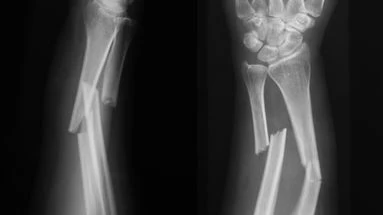

Vous pourrez bientôt réparer votre fracture du bras à l’aide… d’une huître !